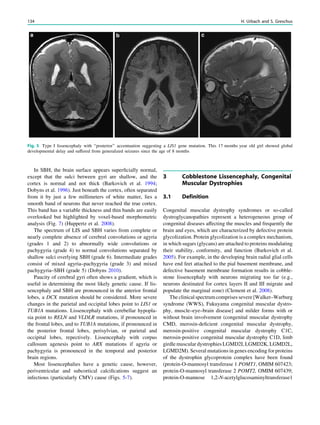

Reversible splenium lesions, 35, 250, 253

Rule of three, 4

S

Sarcoidosis, 216–218

SBH, 134

Schimmelpfennig–Feuerstein–Mims syndrome, 173